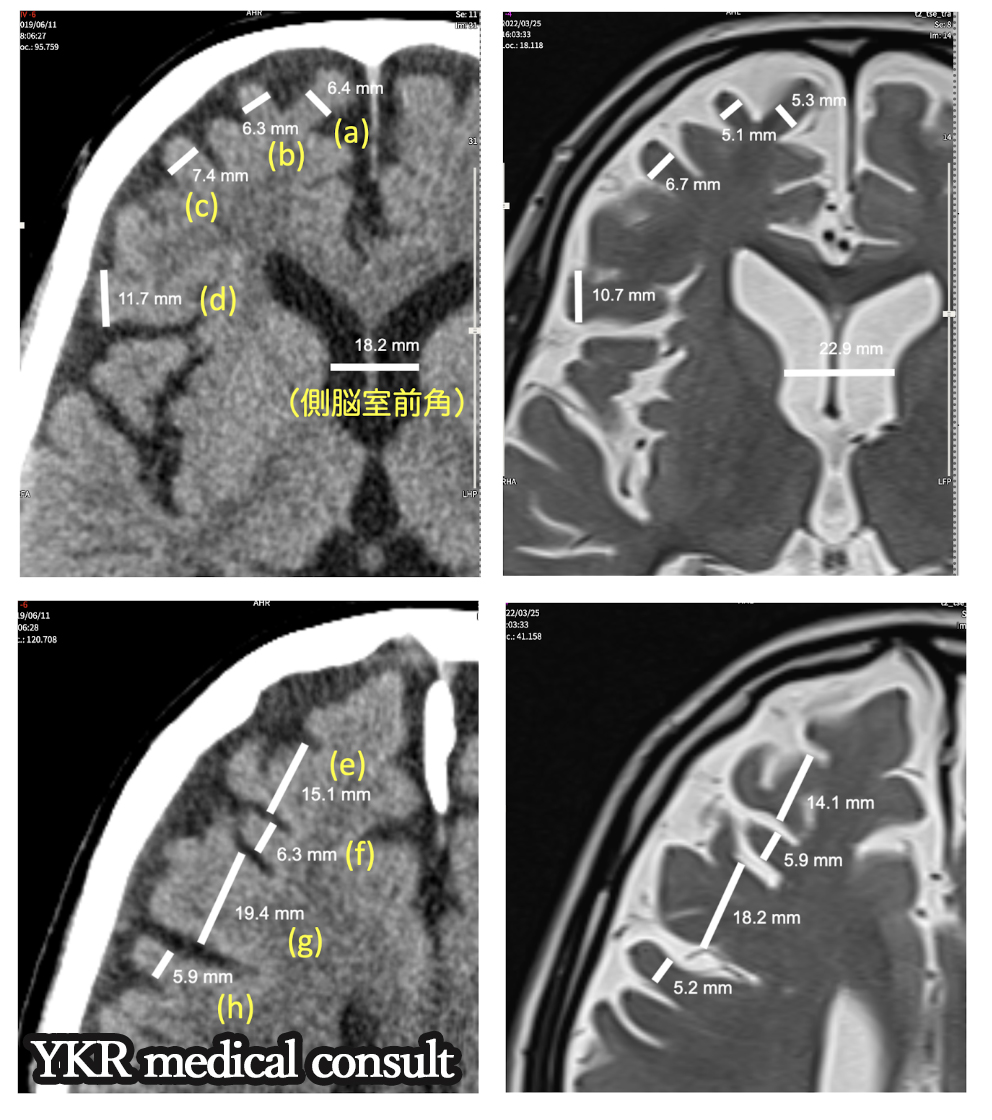

交通事故訴訟・反論意見書・脳神経領域(MTBI)1 依頼内容content(1) 事故および受傷の内容被害者は追突による交通事故で受傷した後に、頭痛・意欲低下を訴えて病院を受診した。その結果頭部MRIにて慢性硬膜下血腫が […]